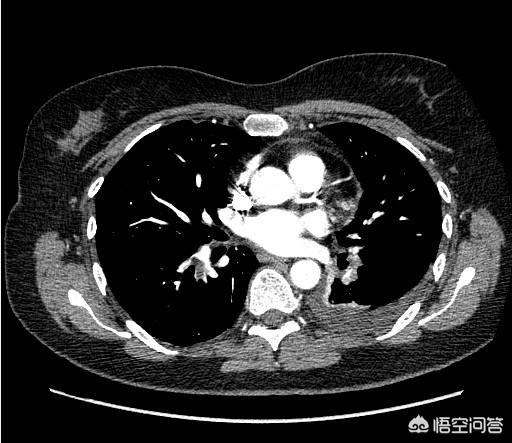

1.腹部全体のプレーンスキャン+強調CT

腹部CTにもplainとenhancedがあることを知らない人が多い。何が違うのでしょうか?腹部全体のCTスキャンは安く、全体像を見るのに数百円です。さらに詳しく見るには、造影・強調CTを受ける必要があります。造影・強調CTとは、検査中に血管に薬を注入し、動脈や静脈の血管を強調CT画像で可視化するものです。すべての腹部臓器には血液を供給する血管があるため、プレーンCTよりも各臓器が鮮明に映し出されます。

例えば、私は外来で患者を診察している。その患者はまず超音波検査を受け、肝臓に特徴的でない腫瘤を発見する。このとき、プレーンCTだけでは、腫瘤の性質を判断することができないかもしれません。スキャン+強調CTでは、造影剤を使わないスキャンCTで腫瘤がどのように見えるかを観察することができます。造影ありの場合は、肝臓の血管を造影剤で満たしたときに腫瘤がどのように見えるかを観察します。肝がんの画像的特徴に基づいて、その腫瘤が肝がんであるかどうかを判断します。

プレーンCTとエンハンストCTを組み合わせることで、腹部の腫瘍を動的に見ることができる。腹部の臓器は固形臓器と中空臓器に分けられ、CTは胃の固形臓器(肝臓、膵臓、脾臓など)によく効き、中空臓器(消化管、尿管など)には効きにくい。そのため、胃カメラと大腸カメラという2つの検査を追加する必要がある。

I. 胸部低線量スパイラルCT

- この低線量スパイラルCTは主に肺がんのスクリーニングに用いられる。肺がんはわが国で最も罹患率、死亡率の高いがんであり、人間ドックでも肺を見逃すことはできない。

- 低線量スパイラルCTは、従来のCTに比べて放射線量が少ないため、肺癌のスクリーニングに適している。

- 現在、肺に小さな結節を見つける人が増えているが、これは検診を受ける人が増えたことが原因かもしれない。検診を受けていない人に比べ、検診を受ければ肺結節をいち早く発見でき、定期的に検診を受けることができます。 肺結節が悪性かもしれないと医師が疑えば、適時に手術を行うことができます。

肺がん検診胸部X線検査および胸部CT検査。

胸部X線検査は、簡便で経済的、かつ迅速な検診として一般的に行われている。45歳以上で喫煙歴のある人や肺がんの家族歴のある人は、解像度が高く肺の小さながん病巣をスクリーニングできる薄層らせん強調CTを受けることが推奨される。胸部X線写真で肺結節が発見された場合は、通常、明確化のためにさらなる強調CTが必要であり、肺癌が強く疑われる場合は、明確化のために穿刺生検が必要である。